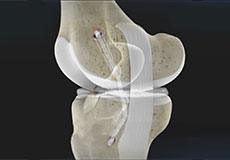

Articular Cartilage and Menisci of the Knee

Movement of the bones causes friction between the articulating surfaces. To reduce this friction, all articulating surfaces involved in the movement are covered with a white, shiny, slippery layer called articular cartilage. The articulating surface of the femoral condyles, tibial plateaus and the back of the patella are covered with this cartilage. The cartilage provides a smooth surface that facilitates easy movement.

Within the knee joint, between the femur and tibia, are two C-shaped cartilaginous structures called menisci. Menisci function to provide stability to the knee by spreading the weight of the upper body across the whole surface of the tibial plateau. The menisci help in load-bearing i.e. it prevents the weight from concentrating onto a small area, which could damage the articular cartilage. The menisci also act as a cushion between the femur and tibia by absorbing the shock produced by activities such as walking, running and jumping.

Chondral or Articular Cartilage Defects

The articular or hyaline cartilage is the tissue lining the surface of the two bones in the knee joint. Cartilage helps the bones move smoothly against each other and can withstand the weight of your body during activities such as running and jumping.